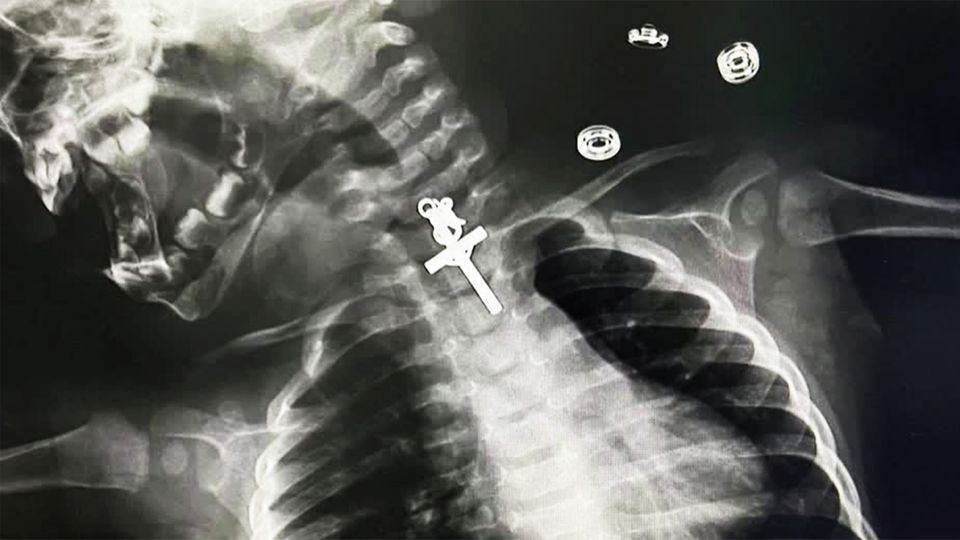

Diese Röntgenaufnahme ist von einem 10 Monate alten Mädchen, das in Peru ein Kruzifix verschluckt hatte. Zum Glück konnten die Ärzte das Objekt erfolgreich entfernen. Die Mutter zeigte sich nach der OP entsprechend erleichtert. Maricarmen Sajami Rosas: "Ich danke den Ärzten für ihre wundervolle Arbeit. Es ist wie ein Neuanfang, ein Geschenk, ein Segen, ein Wunder, dass sie meine Tochter gerettet haben." Auch die Ärzte waren froh, dass der Eingriff glimpflich verlief. Denn die Operation war, laut ihrer Darstellung, relativ kompliziert, besonders durch die Form und die Position des Kreuzes, das im oberen Teil der Speiseröhre festsaß. Sie brauchten mehrere Anläufe. Aber am Ende ging alles gut. Und das Kind ist wieder wohlauf.